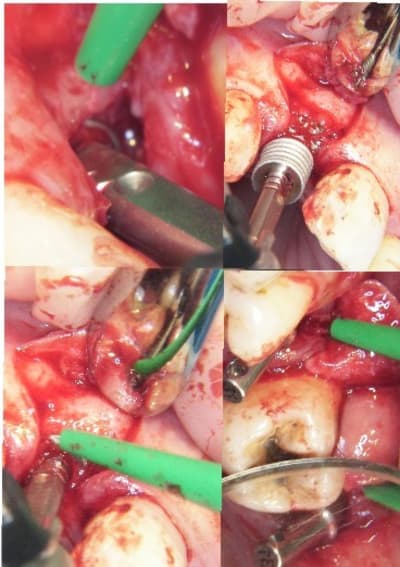

j'ai fait une bonne matinée implanto ce matin avec mélange des techniques 2 Summers avec un mélange expanseurs/condenseurs Meissinger, ostéotomes impactés pour la corticale qui faisait de la résistance, eponge pour la membrane, puis une reprise d'echec sur une mise en vitrine immédiate (fracture en mangeant une frite calcinée, à un mois!le 14/07)déposé le 15/07 mais avec mouvements pendant 24 heure et de 3.4mm j'ai du passer à 5.2!

les photos d'hier avec la mise en vitrine immediate et la reprise

--

xbk